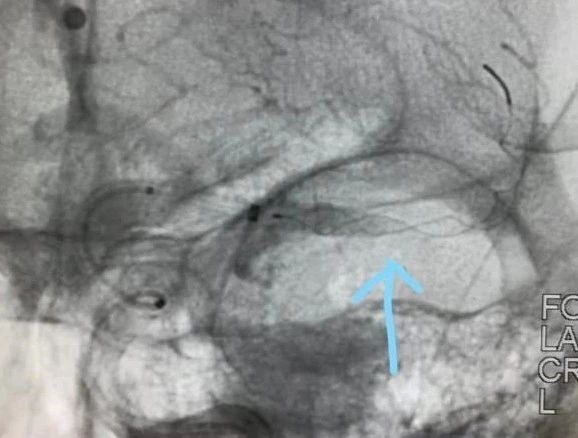

患者发病到入院时间超过4.5h时间,静脉溶栓时间窗超过,考虑大血管病变,患者急诊CT提示左侧大脑中动脉高密度征,ASPECTS评分9分,未见明显低密度灶,结合患者急诊查体,高度提示左侧颈内动脉系统大动脉闭塞。与家属沟通后,急诊行DSA,必要时予血管内治疗。

通过推拉按摩技术后支架打开好转。

术后造影,mTICI分级III。